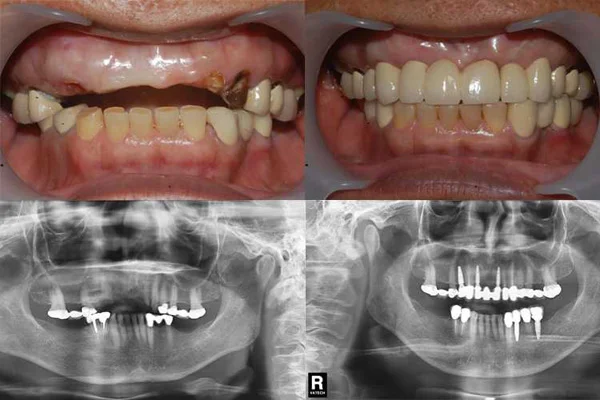

Dental implants case by CM Dental Clinic have won the 1st prize "Prasan Award" Contest b TPDA & DGOI

Dental Implant Treatment cases

The followings are some of dental implant treatment cases by Implantologist Chiang Mai.